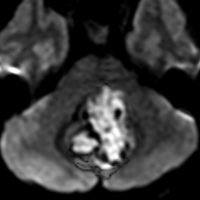

血管芽腫 hemangioblastoma

左の例は延髄から脊髄にのう胞形成するもので,とても大きく手術は超高難易度手術となります。右の例でもかなり困難な手術で,このような血管芽腫の手術の手術を安定した成績でできる脳外科の先生は日本に数人くらいしかいないかもしれません。画像診断の特徴は,血管を描出できる画像をみると,腫瘍の周囲に拡張した静脈がたくさん見えて,血流がかなり多い腫瘍 hypervascular tumorの所見があることです。